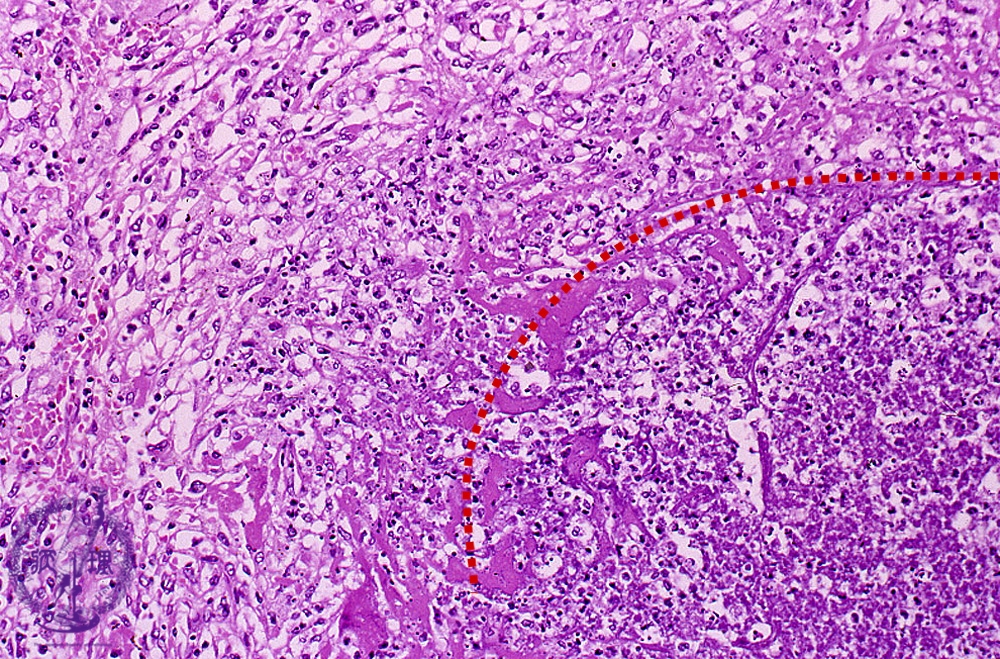

- ★(7)Bacterial pneumonia (lung abscess)

Microscopic view (HE stain, high power view): On the right, there is abscess composed of inflamed necrotic debris (dotted line) surrounded by granulation tissue (left). Granulation tissue consists of fibroblasts, inflammatory cells and capillaries.